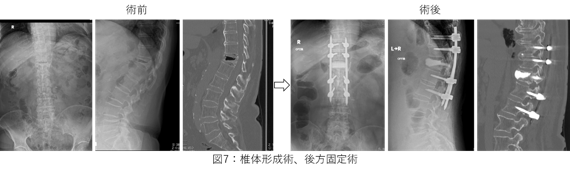

まずCT、MRIにて骨折の程度を評価するともに、この骨折による骨片で脊髄が圧迫されているかどうかを確認します。どれだけ脊髄が圧迫されているか、および実際に脊髄が圧迫されてどれだけ下肢に痛みやしびれ、麻痺が生じているかなどから、コルセットなどの保存加療を選択するか、手術を選択するかを決断します。

手術の際には骨セメントを用いた椎体形成術、スクリューを用いた固定術、脊髄の圧迫を解除する除圧術、これらを組み合わせて行います(下図7)。近年この椎体形成術および固定術は小さな皮切で経皮的に行うことが可能ですので、可能な範囲で少しでも低侵襲な手術を目指しております。